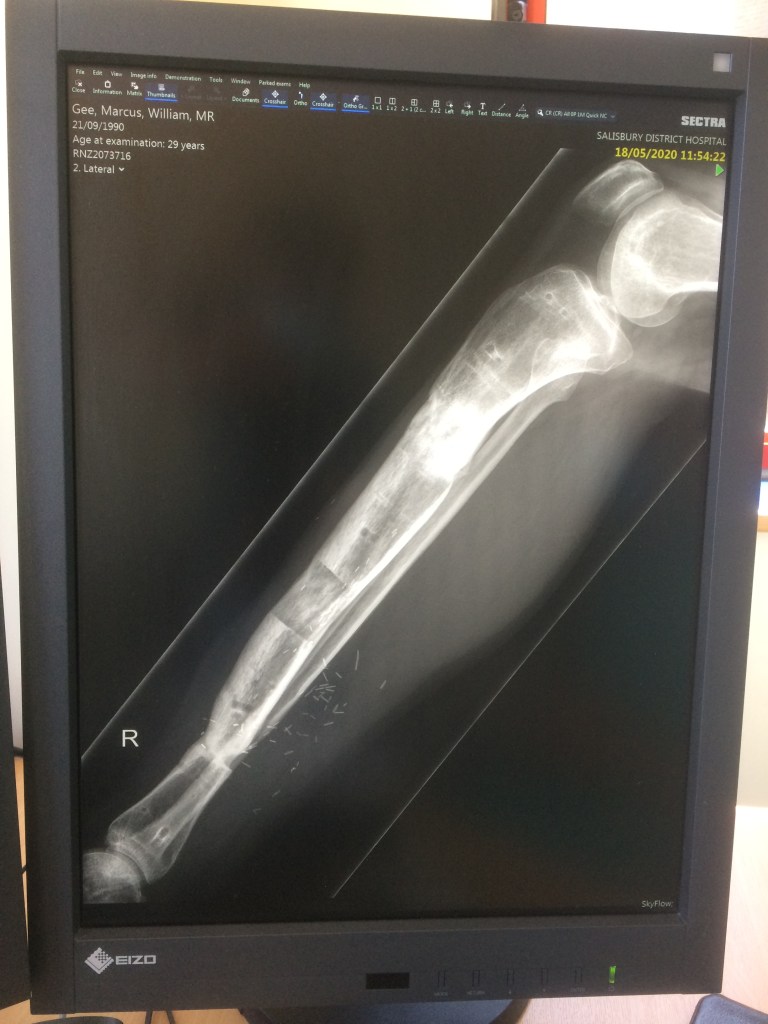

You can see in these x-Rays that the new bone was still quite soft…

IMG_1087